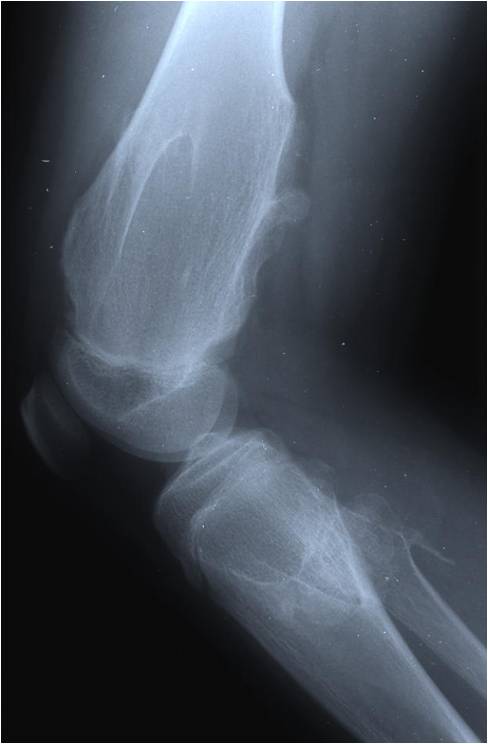

Radiographic Presentation

Plain X-rays:

- Projects from bone with narrow (pedunculated) to broad (sessile) stalk

- Corticomedullary continuity: Medullary bone continuous with that of osteochondroma and cortex blends with that of osteochondroma

- Calcification in cartilaginous cap (“Ring and Arc” and stippled calcifications)

- Lobular growth pattern

- Long bones: arise from metaphysis, grows away from epiphysis toward diaphysis,

Dysplasia Episphysealis Hemimelica – Trevor Disease

- Ankle and knee most common

- Medial joint 2X lateral

- Lobular epiphyseal mass

- Histologically identical to an osteochondroma

- May produce deformity and secondary osteoarthritis